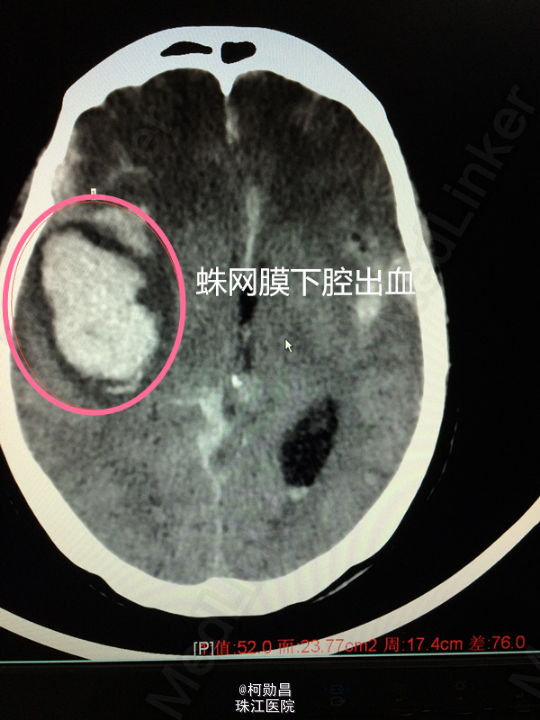

主诉:突发意识障碍7小时 病史:患者于早上7时被发现意识不清,神志呈浅昏迷状态(GCS6分),立即被送往当地医院,急查头颅CT提示:1、右侧颞叶脑出血;2、蛛网膜下腔出血病四脑室积血;3、中线结构轻度左移(0.3cm)。立即予器官插管呼吸辅助通气、止血、抗血管痉挛、维持水电平衡、营养神经的个治疗。后为进一步治疗转入我院。

诊断:蛛网膜下腔出血破入脑室:动脉瘤? 处理:急诊予全脑血管造影提示:右侧大脑中动脉分叉处动脉瘤,予介入栓塞治疗(弹簧圈),并予去骨瓣减压术治疗。